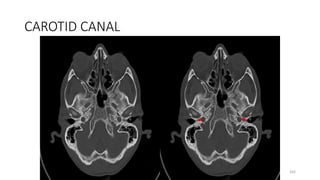

CAROTID CANAL

162

183